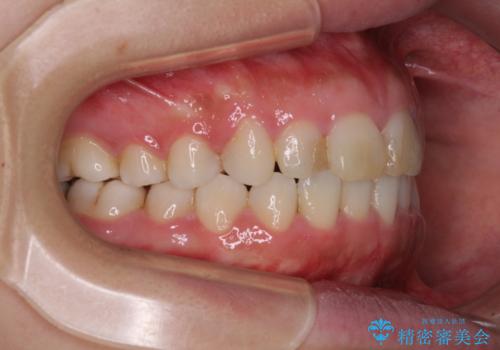

- ワイヤーではない矯正治療があると聞いたとのことで来院された患者様です。

長年前歯のデコボコを気にしていたもののワイヤー矯正に抵抗があり躊躇していたそうですが、インビザラインなら治療してみたいとのことで相談にいらっしゃいました。

インビザライン適用の歯列であったため、歯と歯の間を削るIPRを用いて改善することとしました。

お仕事柄、長時間のマウスピース装着が苦ではなかったので、歯列はすぐに整いましたが、ゆっくりとした交換頻度であったので、2年ほどの治療期間を要しました。